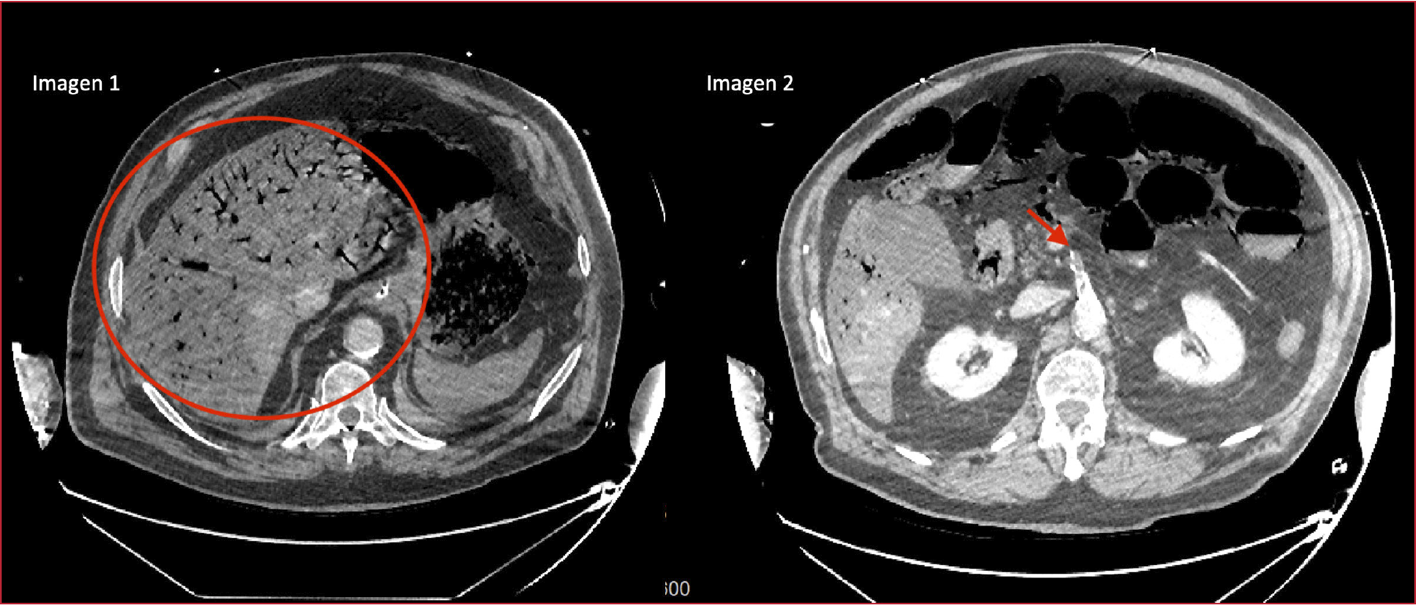

Se procedió a

la intubación orotraqueal y la estabilización. Se realizó una tomografía

computarizada abdominal. En las imágenes, se detectó neumatosis intestinal y

portal masiva (Figura, círculo rojo) secundaria a isquemia intestinal por trombosis de

la arteria mesentérica superior (Figura, flecha roja).

Figura. Neumatosis portal masiva secundaria a isquemia intestinal masiva.